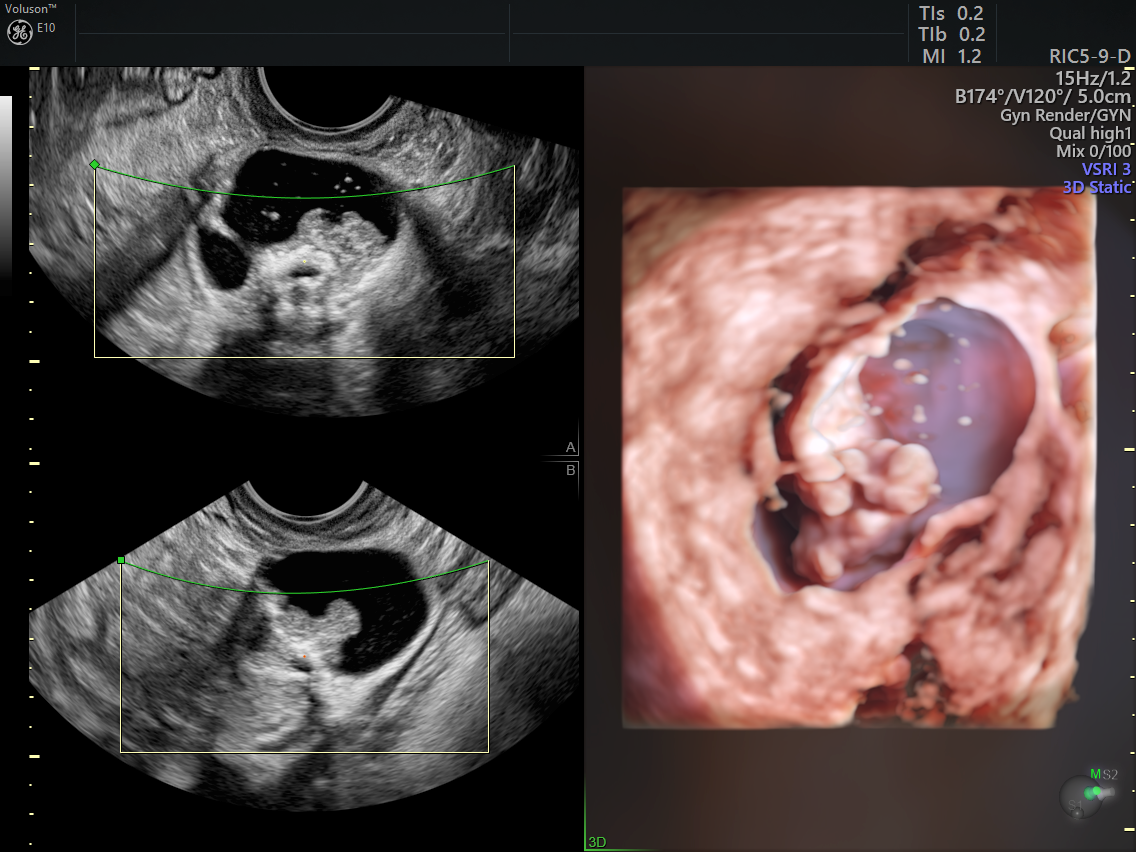

🔹 3. Ecografía ginecológica

Permite detectar de forma temprana:

Miomas uterinos

Quistes ováricos

Síndrome de ovario poliquístico (SOP)

Alteraciones endometriales

👉 Muchas de estas condiciones no generan síntomas al inicio.

Primera ecografía temprana si ya existe embarazo

Tecnología ecográfica avanzada